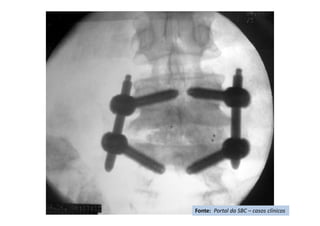

Apresentação de Casos Clínicos

• Escoliose Idiopática do Adolescente

• Resumo do caso: Escoliose idiopática do adolescente tratada

cirurgicamente com artrodese da coluna T4L1 com parafusos

pediculares.

• Paciente (dados): feminino, 13+2 anos, Risser 3, menarca há

9 meses.

• História: Deformidade da coluna percebida pela mãe há 3

meses. Nega tratamento prévio. Nega demais doenças ou uso

de medicações.

• Diagnóstico(s): Escoliose idiopática do adolescente, Lenke

1B-. Tratamento(s): Artrodese da coluna por via posterior T4-

L1 com parafusos pediculares.

• Seguimento ("Follow up"): Seguimento de 2

anos. Literatura:

• Resultado Final: Artrodese seletiva torácica T4-L1, obtida

compensação do tronco e nivelação dos ombros.

Fonte: Portal da SBC – casos clínicos

Radiografia pós-operatório -AP